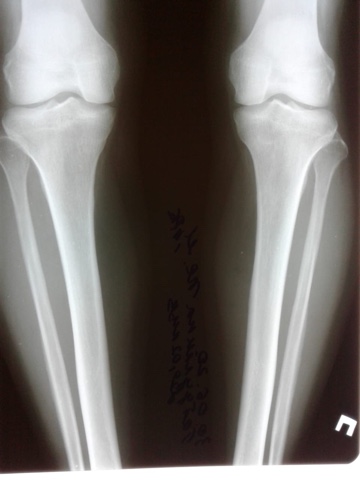

Исходник - 34 года.

Дата операции -- 03.07.2020